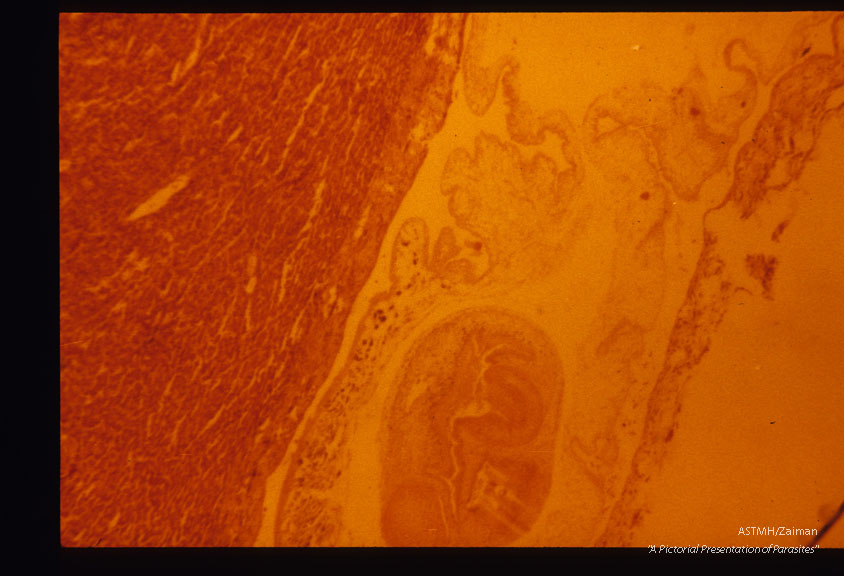

Usually the cysticerci of this tapeworm are found in rabbits. Very rarely they may be found in the definitive he (dog). This is such a case with slide (1867) showing gross and slide (1868) the microscopic pathology.

Taenia pisiformis

Description: Usually the cysticerci of this tapeworm are found in rabbits. Very rarely they may be found in the definitive he (dog). This is such a case with slide (1867) showing gross and slide (1868) the microscopic pathology.